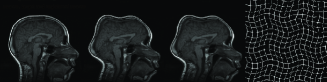

In Figure 9, three example registration results of randomly and nonlinearly warped images are shown. Capturing signal intensity variations during registration process with intensity standardization method leads to assesment of visual comparision of registered source and target images with warping grid. Evaluation of the registration results is summarized in Table-2. The table shows that large and small scale deformations are captured accurately on the standard intensity scale. Resulting images have fixed intensity meanings even there is large intensity variations initially.

Figure 9: Resulting registration of images with random nonlinear warps. Each row includes source, target, registered source and estimated warping grid

Refer to caption

The resulting registered images and deformation fields show that standardization of intensity scales improves the accuracy of registration.